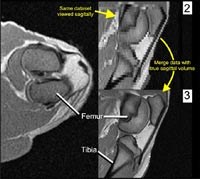

To allow the registration and integration of these different types of data, it was necessary to fix the limb in a rigid medium to inhibit movement about the knee so that it would be in the same relative position in the different scans. This was accomplished using an expandable, insulating foam, which is of extremely low density and quite rigid when cured (Figures 1 and 2).

Figure 2

The limb, now embedded in a foam block, was then scanned in CT and MRI at O'Bleness Memorial Hospital in Athens, Ohio. The CT scans were performed on a GE HiSpeed Fx-i Helical CT scanner (120.0 kV, 100.0 mA, axial slice thickness of 1 mm). MR imaging was performed on a 1.0T GE Signa Short-Bore MRI system (T1, axial and sagittal slice thickness of 3 mm). The entire hindlimb was CT scanned, but the MR field of view was limited to the knee region. The scan data were then imported into a computer workstation, and analyzed using Amira 3.1 (TGS, Inc., San Diego). Because the 3mm slice thicknesses of the MRI datasets are rather coarse for generating 3D models, the axial and sagittal MR datasets were combined and resampled to produce a composite volume of 1mm intervals (Figure 3).

fig3

Figure 3

To produce a single dataset from separate CT and MR volumes, we merged the two datasets. Since both datasets provide at least some information on similar structures (muscle, for example), we stripped away the redundant data. In other words, we removed all of the grey values that were less dense than bone from the CT volume (e.g., soft tissue, air), and from the MR volume we removed anything below the soft-tissue threshold (Figure 5).

fig5

Figure 5

We then resampled, or resliced, the MR data set so that each slice in the MR volume corresponded directly to a slice at the same position in the CT dataset. Once this was done, we were able to merge the two datasets, which essentially blends a given CT slice with the corresponding MR slice. The result is a single dataset with bone from CT and the soft tissue from the MR.